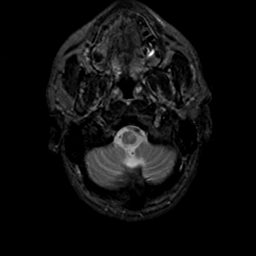

MR Study #19, August 25, 1991 -- Slice #4

[Home][Help][Clinical][Tour 1][Tour 2] Slice 4